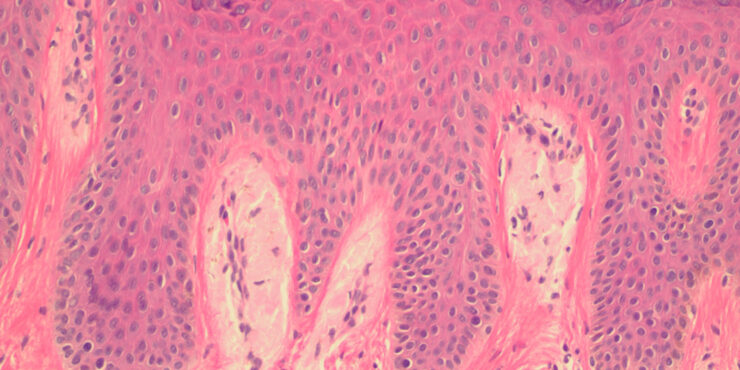

Lentigo maligna melanoma = ميلانوم الشامة الخبيثة Lentigo Maligna Melanoma Lentigo maligna, previously referred to as melanosis circumscripta preblastomatosa of Dubreuilh and also as melanotic freckle of Hutchinson [or Hutchinson’s melanotic freckle (HMF), a term used currently in Australia for this condition], accounts for about 10% of melanomas and typically occurs on the chronically exposed […]